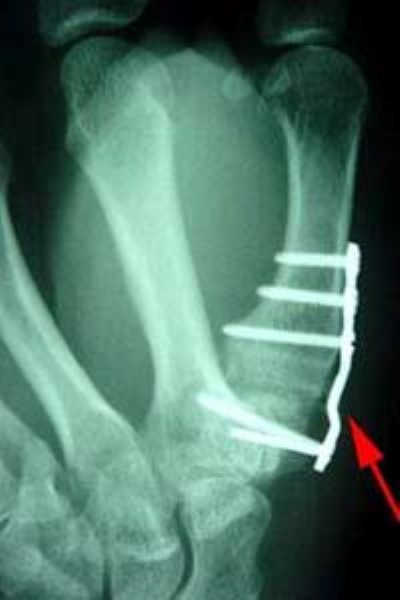

X-ray of joint fusion at base of thumb

A joint fusion using a plate and screws at the base of the thumb.

Joint fusion. Joint fusions provide pain relief but stop joint motion. The damaged joint surfaces are gone, so they cannot cause pain and other symptoms. However, because there is no longer a joint, the motion provided by that joint is no longer possible. Thus, these surgeries may reduce function while relieving pain. In some joints, this loss of function is unimportant. In other joints, the limitations of the fusion are obvious and challenging, possibly affecting quality of life.